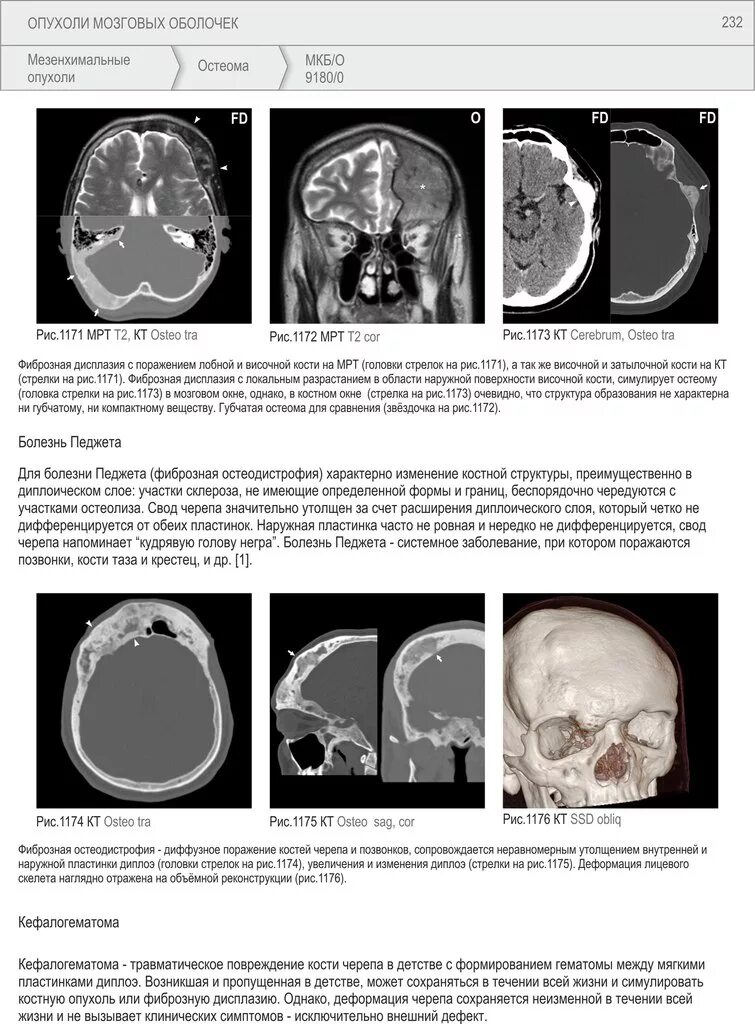

Химиотерапия при раке головного мозга